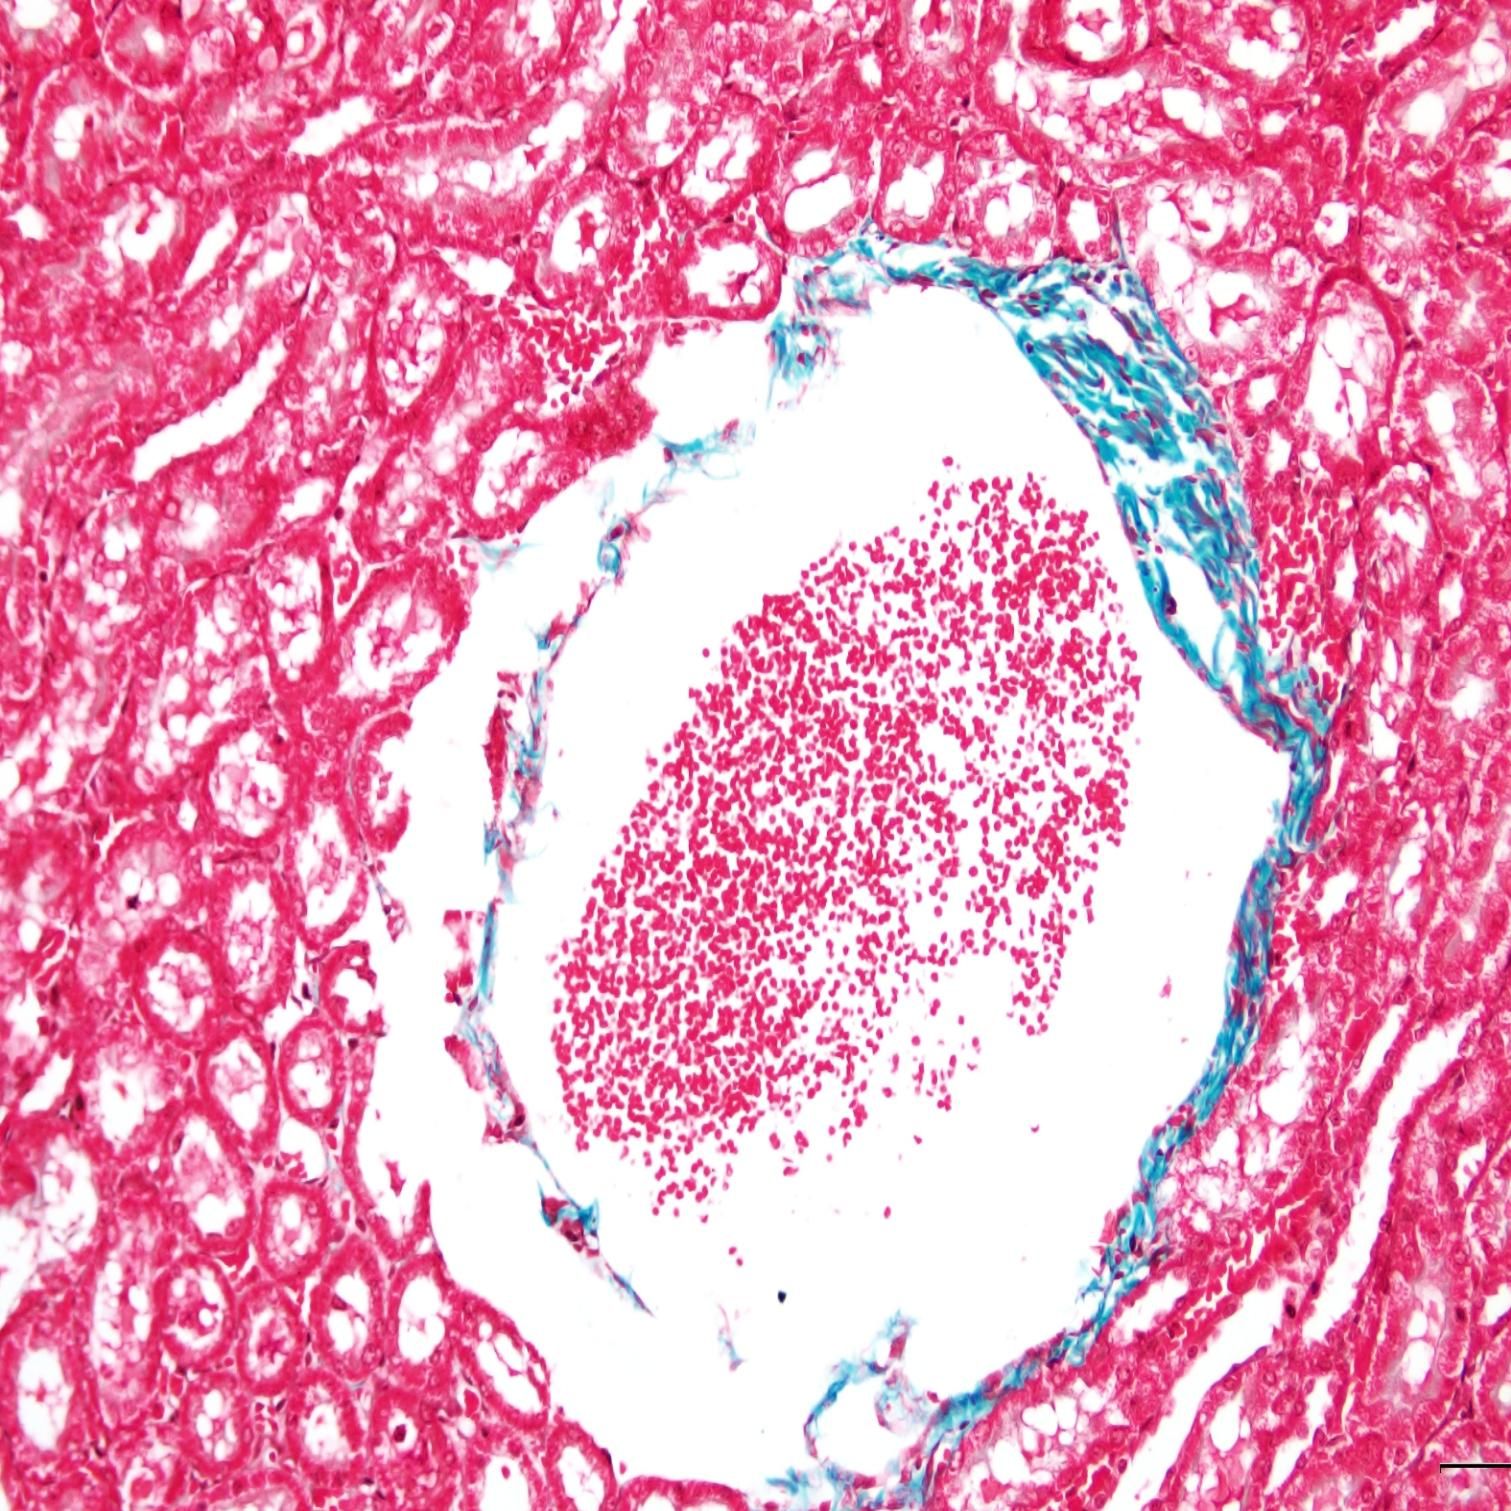

在組織學研究中,MASSON染色可以幫助我們觀察和分析不同組織類型的形態和分布。例如,在肌肉組織研究中,MASSON染色可以清晰地顯示肌纖維的走向和排列方式,為我們揭示肌肉組織的生理結構和功能提供有力支持。

小鼠心肌染色

②病理學診斷

在病理學診斷中,MASSON染色同樣發揮著重要作用。通過MASSON染色,我們可以觀察到病變組織中膠原纖維的增生、變性等變化,為疾病的診斷和治療提供重要依據。